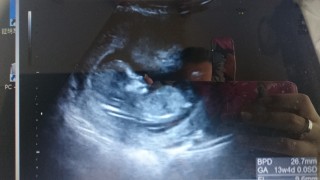

初めての経腹エコー! そして、初めての動いているところが見れました(●´ω`●) 人間らしくなってるだけで感動していたのに、動く姿まで見ることできて更に感動!エコー動画も貰えたので、何回も繰り返し旦那と見てます笑毎日寝る前に見たいって言ってました笑 これからの成長も楽しみです!

CRL66.6です。 頭の大きさは3㎝くらいだそうです(*´∇`) ほぼ週数通りですねと言われました! 背骨がスケルトン(笑)! まだ性別はわかりませんでした。 最近、体調を崩してあまりご飯が食べれなかったり、貧血になることもありましたが、お腹のなかで順調に育っていることもわかりひと安心。 仕事もあまり無理しすぎないように頑張りたいと思います(^^;

13週0日の70ミリ。 終始動きっぱなしで子宮のなかでぴょんぴょんしてる落ち着きのないベビです笑 元気いっぱいで、胎動を感じるのが待ち遠しいです!